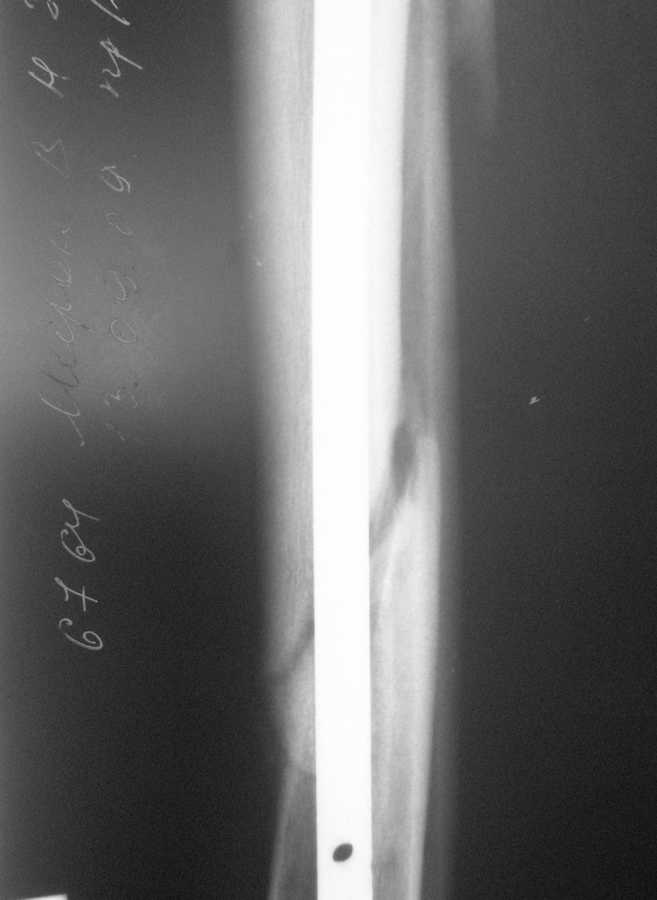

В январе 2009 года нами оперирована пациентка с переломом н\3 голени штифтом Expert. Динамизация через 4 месяца, пациентка при этом уже ходила с тростью. Дома периодически передвигалась без дополнительной опоры. В настоящее время - через 9 месяцев с момента операции периодически в вечернее время беспокоят ноющие боли в места перелома (не постоянно). При беседе выяснено, что боли чаще беспокоят после того, как днем она походит по дому без трости. Пальпаторно по гребню берцовой кости болей нет, но по задне-внутренней поверхности б\б кости пальпирутеся западение на уровне места перелома.В чем ошибка??? и что делать???

Недостаточная стабильность. Не использованы все возможности дистального запирания, нет самого проксимального из дистальных винтов. Два винта из трех коротковаты. В результате при диинамизации появился диастаз.

Тут есть уже опасность перелома стержня по ближайшему к перелому отверстию. Так что правильнее сделать реостеосинтез с рассверливанием. При введении гвоздя в дистальный отломок использовать отклоняющую спицу

или винт, чтобы стержень оказался не у переднего кортекса, как сейчас, а где и надо - посередине. Это обеспечит еще и встречно-боковую компрессию.

Значит, изначально в периферическом отломке гвоздь шел не по центру, а ближе к передней стенке. Это не очень хорошо.

Да, динамизация поздновата. Да дистальный отломок заперт одним винтом, два другие короткие, еще дно отверстие пустое...

Этот 9-ти мм. стержень ExpertTN вряд ли скоро сломается, если, конечно же, пациентка не имеет большого веса (>100 kg). Перештифтовать более толстым штифтом с рассверливанием, пожалуй, самый надежный вариант, но не факт, что единственный. Вполне правомочно подумать просто о косой остеотомии малоберцоыой кости (зачем резекция???) в средней 1/3 и попытке дополнительной стабилизации дистального отломка путем запирания штифта через свободное отверстие (наиболее проксимальное из дистальных) и замены двух самых дистальных винтов, причем косой самый дистальный лучше провести в другой плоскости. Возможно этого будет вполне достаточно для сращения...а вот периодически возникающие боли могут и остаться(((

По снимку гвоздь сидит плотно в узкой части большеберцовой, а на периферии нестабильная блокировка. Динамизация работает в течение первых 8 недель.